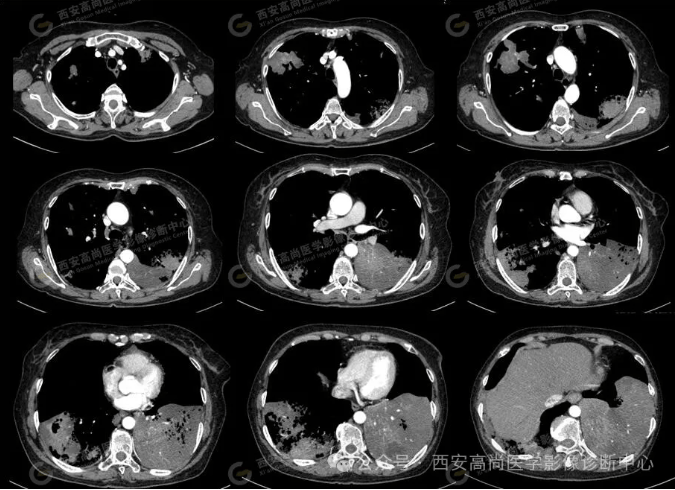

pet/ct病例—肺粘液腺癌,历经3年余终确诊【西安高尚医学影像诊断中心